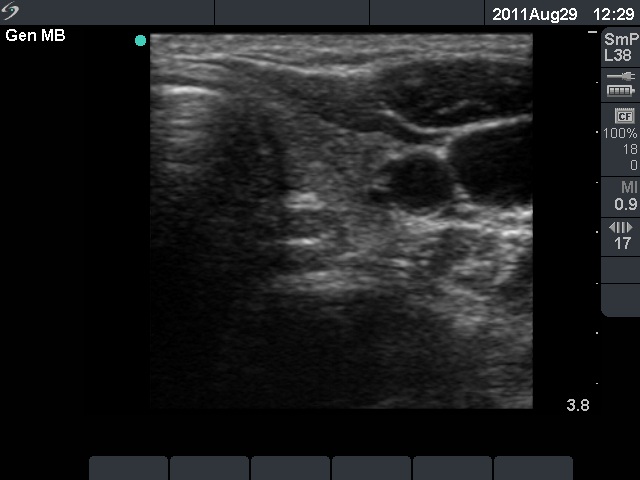

Follow-up examination 3 years later (second row of images):

Ultrasonography: The thyroid was unchanged. The lesions in the dorsal part of the right lobe increased in size and a small hypoechogenic area appeared in the ventral part of the left lobe.

Aspiration cytology was performed from the lesion in the dorsal part of the thyroid. We gained only scattered number of epithelial cells without any atypia.

Wash-out thyroglobulin and parathormone levels were determined, the former was 74.4 ng/mL while the latter was above 474 pg/mL.

A repeat blood test was performed. Serum thyroglobulin resulted in 11.9 ng/mL while serum parathormone level did in 180.7 pg/mL. Serum calcium was 2.94 mM/L, serum phosphorus 0.69 mM/L.

Scintigraphy disclosed parathyroid enlargement not only in the right but even in the left side.

Surgery was performed. Histopathology disclosed hyperplasia of all four parathyroids.